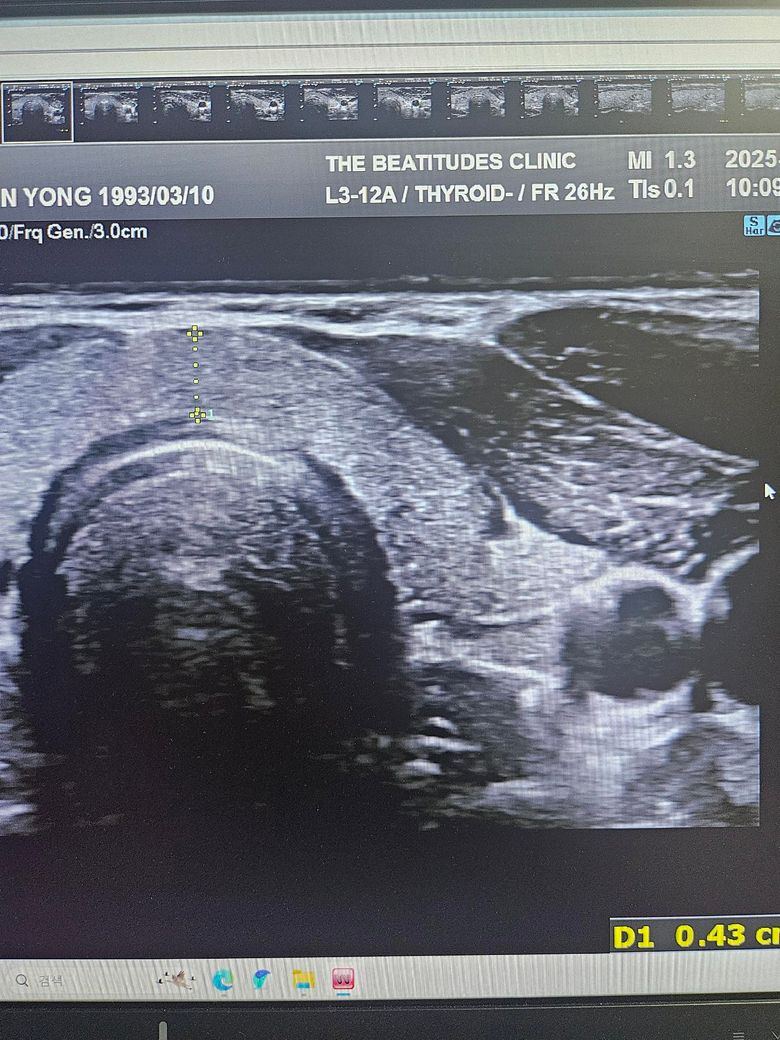

갑상선초음파하고 세침검사 권유받았는데 위의 세개의 사진은 같은 혹이 맞는건가요? 1개 있다고 얘기해줘서 봤는데 사이즈가 이렇게나와서 가로 세로 폭 값인건지 여쭤보고싶습니다

첫번째 사진과 세번째 사진의 경우 같은 결절로 보입니다.

초음파에서 첫번째, 세번째 사진의 급성 연골 오른쪽에 위치한 오른쪽 갑상선에 동그란 혹이 관찰되며 사진으로는 사이즈를 정확하게 구하기 어렵지만 1.5 cm 이상으로 보이며 혹 안에 균질하지 않은 모습으로 악성 혹은 양성이라고 해도 정기적으로 관찰해야 하는 종양으로 보여 조직 검사를 받는 것은 필요한 것으로 보입니다. 갑상선 종양은 다른 종양에 비해 예후가 좋아 적절한 치료를 받으면 대부분 완치가 가능합니다